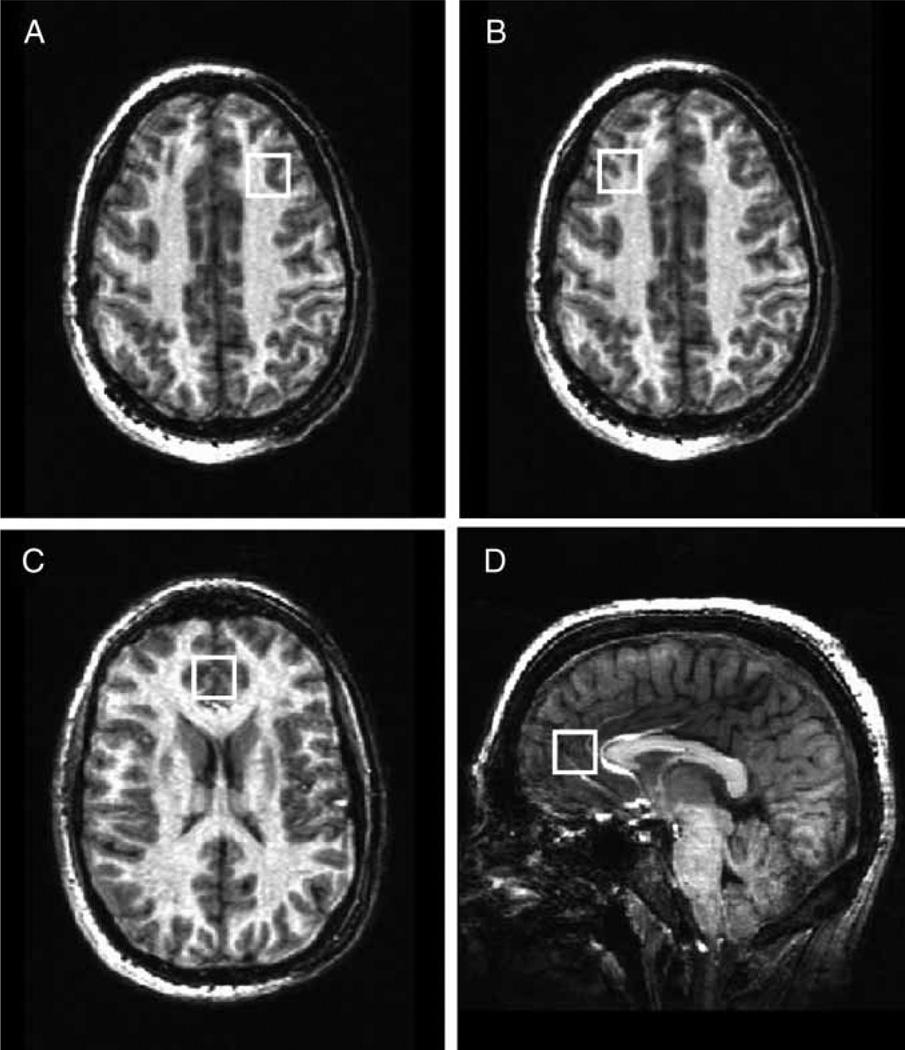

Magnetic resonance imaging (MRI) and 1H MRS data were acquired on a Varian 4 T whole-body scanner (Varian Inc., Palo Alto, CA, USA). A 1H TEM (Transverse ElectroMagnetic) head coil was used as a transmitter/receiver. A multi-slice scout image was initially acquired for MRS voxel positioning. The scout image was followed by the acquisition of three-dimensional whole-head MRI using MDEFT (Modified Driven Equilibrium Fourier Transform) pulse sequence for tissue segmentation.34 After MRS voxel positioning, the magnetic field homogeneity was optimized using an automatic shim method FASTMAP (Fast Automatic Shimming Technique by Mapping Along Projections).35 A typical water line width in the MRS voxel was 10–12 Hz. Three single-voxel PRESS (Point RESolved Spectroscopy) spectra were collected in bilateral (BA32/33) and R/L-DLPFC, BA9 (Fig. 1). Spectra were acquired with repetition time 2000 ms, echo time 23 ms, voxel size 8 cc and 64 averages with water suppression by the VAPOR (Variable Pulse powers and Optimizing Relaxation delays) method.36 For computations of metabolite levels and eddy current correction, one reference spectrum without water suppression was collected at the same voxel position with the same parameters except four averages were acquired, and receiver gain reduced.

Figure 1.

Voxel placement in the left (A) and right (B) dorsolateral prefrontal cortex (DLPFC, BA9), and bilateral anterior cingulate cortex (ACC, BA32/33) (C,D).